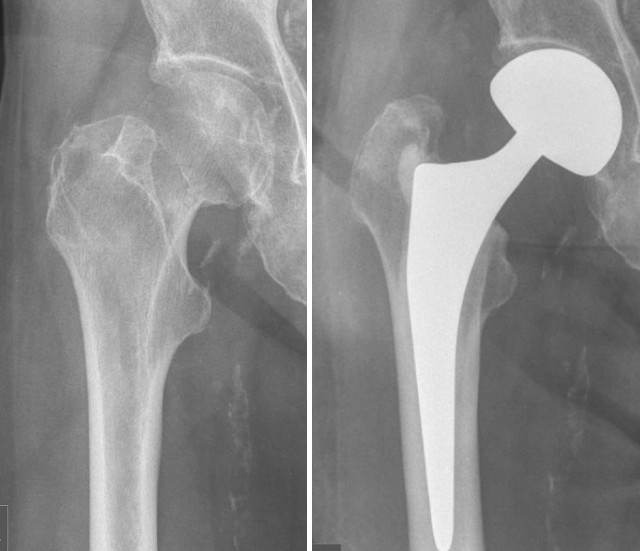

• Top 5 des problèmes brûlants de la fracture du col du fémur, vos pairs s'en occupent !

Top 5 des problèmes brûlants de la fracture du col du fémur, vos pairs s'en occupent !

Choix de la fixation interne par rapport au remplacement articulaire À l'heure actuelle, on pense généralement que la fixation interne par clou creux pour fracture du col du fémur présente les avantages d'une durée d'opération courte, d'un faible traumatisme et d'un faible coût, mais la plupart des patients âgés sont accompagnés d'ostéoporose, de sorte que la stabilité de